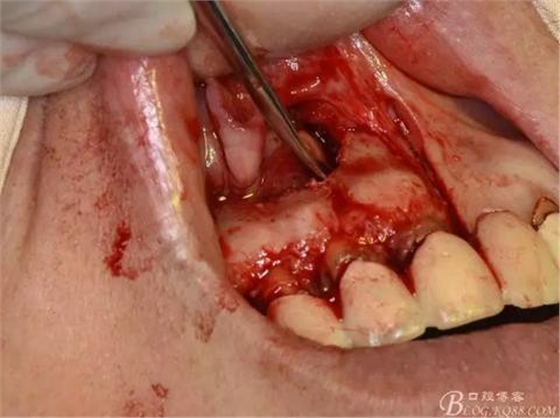

圖10.剝離囊壁